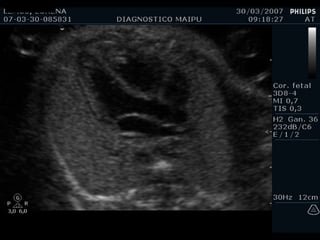

EXAMEN BASICO GENERAL Ubicación Eje Tamaño  Cámaras Pericardio Ritmo VALVULAS AV Apertura y movimiento Inserción AURICULAS Tamaños Flap del foramen oval Septum VENTRICULOS Tamaños Paredes Banda moderadora Tabique

EXAMEN BASICO GENERAL Ubicación Eje Tamaño  Cámaras Pericardio Ritmo

Cámaras COLUMNA AORTA ESTERNON VP VP BANDA MODERADORA FLAP VI VD AI AD

EXAMEN BASICO AURICULAS Tamaños Flap del foramen oval Septum

Tamaños

Flap

Septum

EXAMEN BASICO VENTRICULOS Tamaños Paredes Banda moderadora Tabique

Tamaño

Paredes

Banda moderadora

Tabique